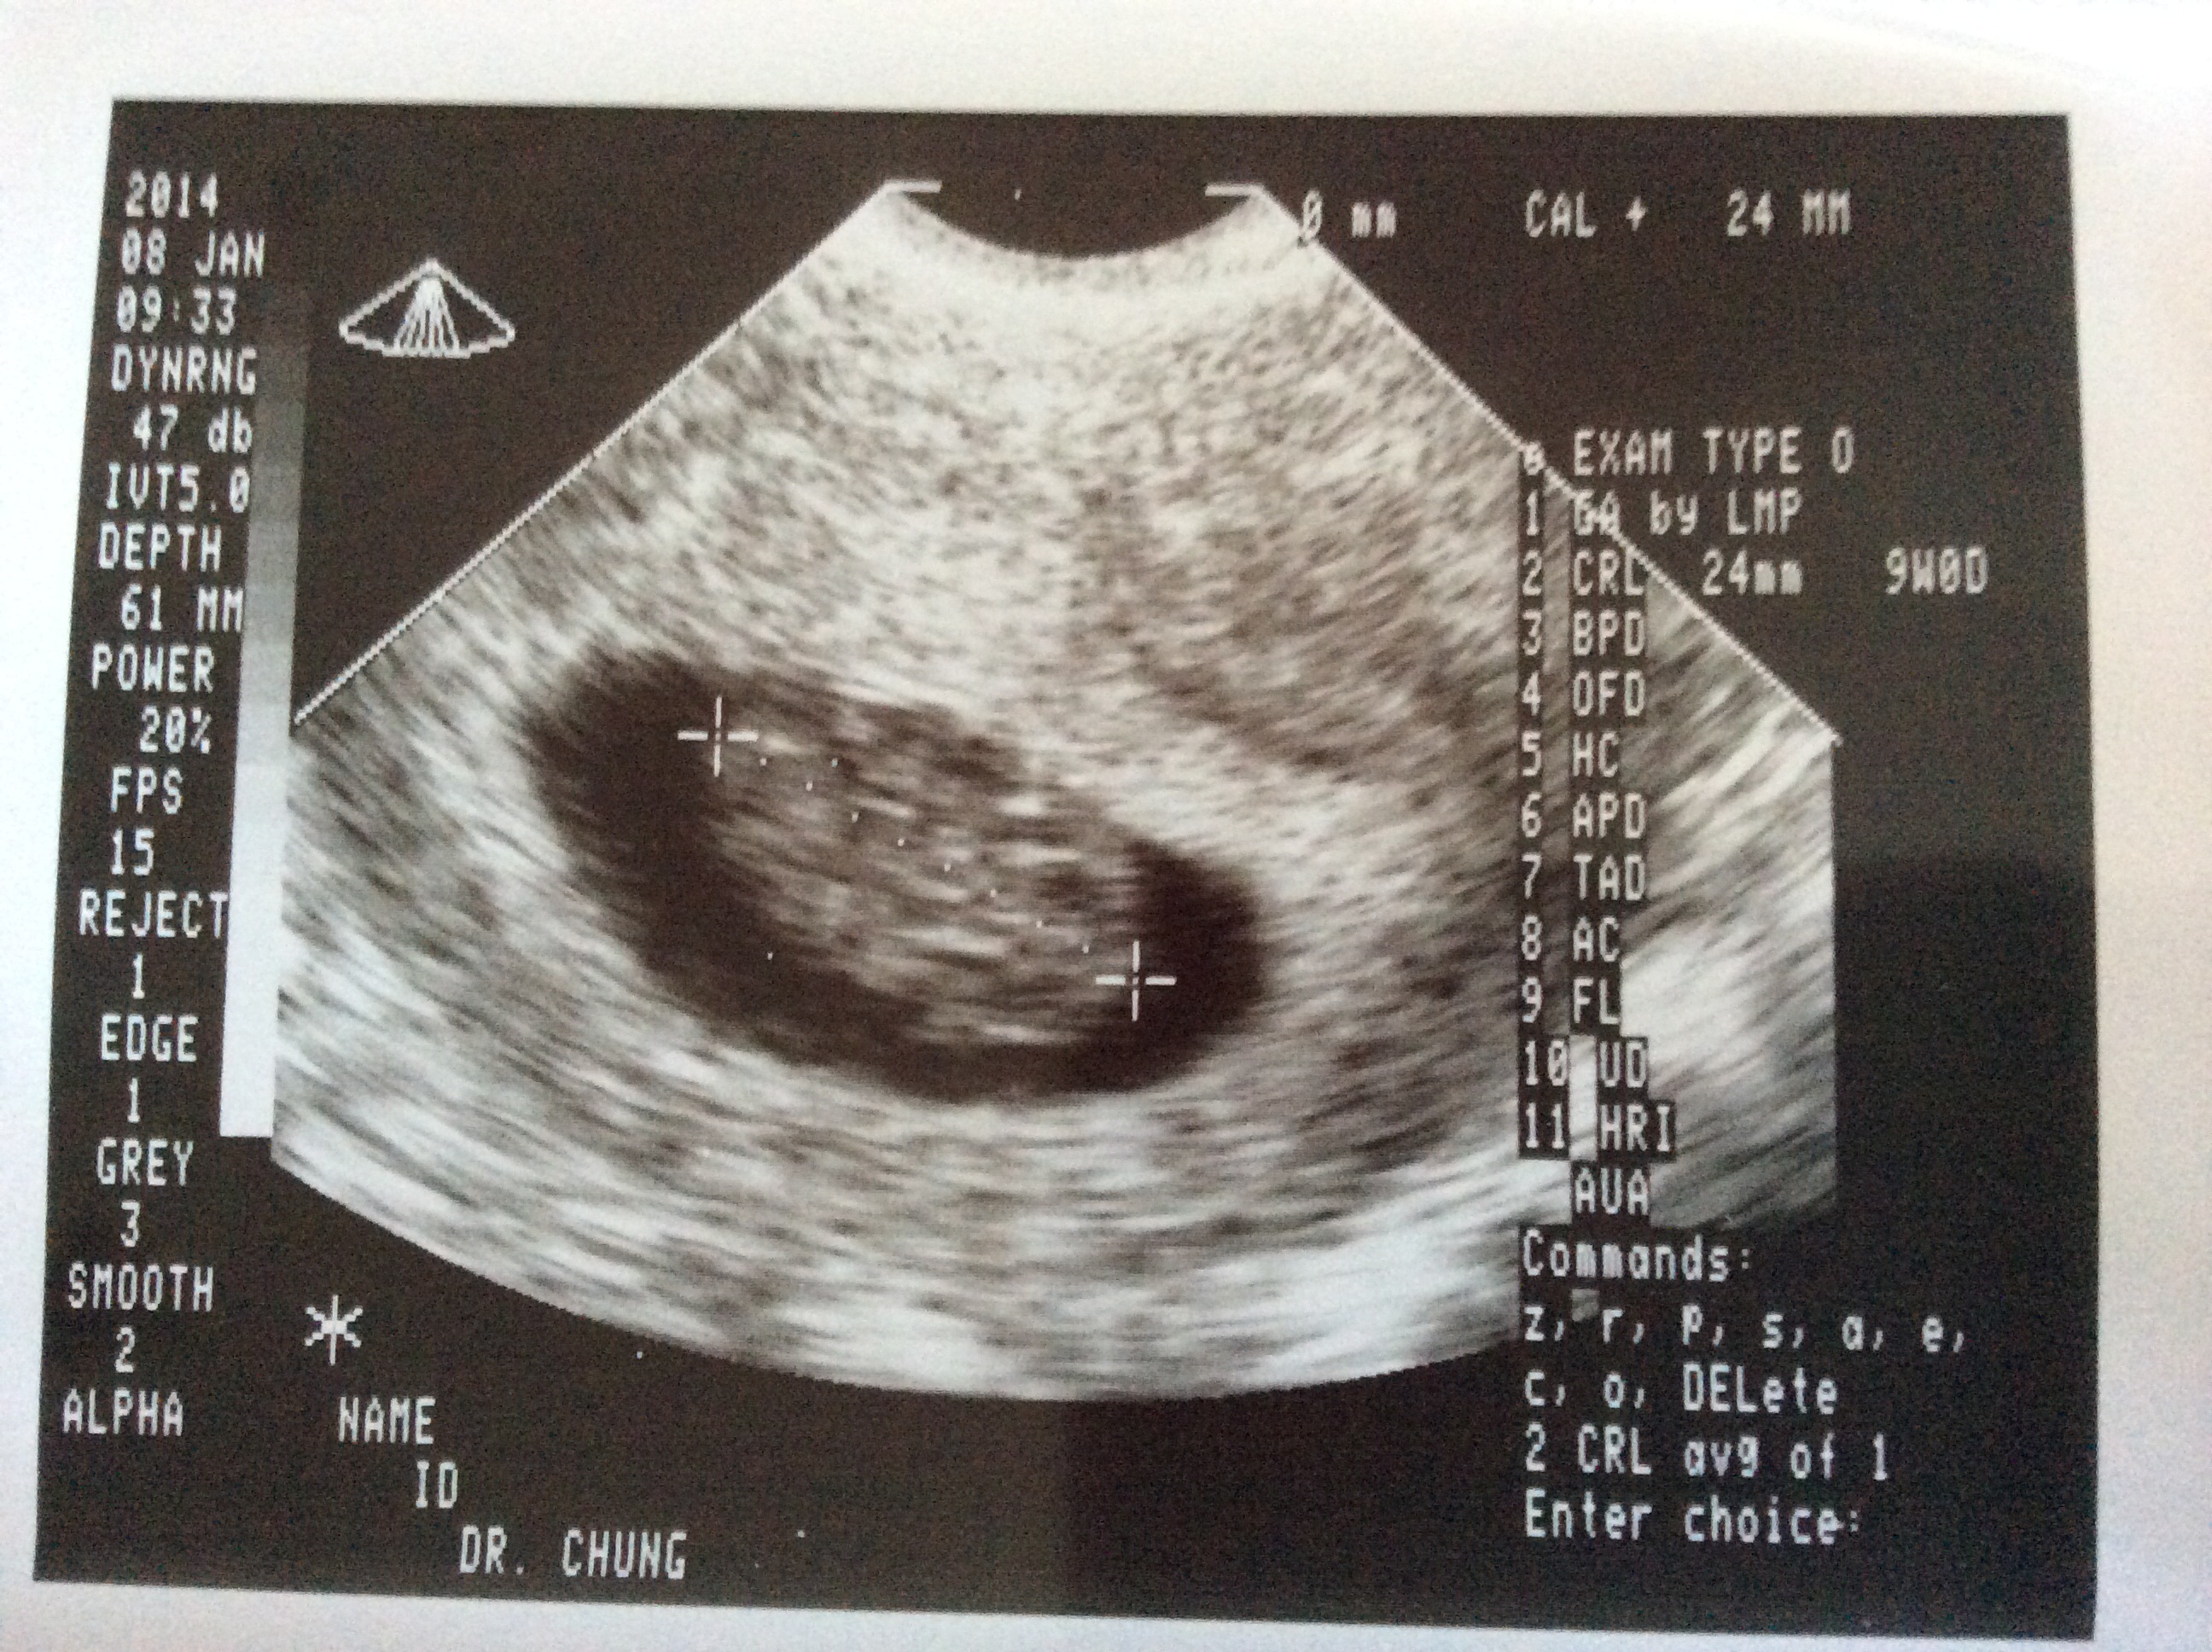

@dkizzire82 - They heard it at my very first trans-vaginal ultrasound at 6 weeks 5 days. Yesterday's was 9 weeks, 4 days. They originally thought I was 10 weeks, 6 days (which I knew I wasn't), but remeasured and confirmed 9 weeks, 4 days. The 10 weeks would have been right on the cusp of being able to hear it with doppler I was told.

I had my first ultrasound on Tuesday morning at 9 weeks 6 days....saw the heart beating on screen...168 beats per minute and measurements were right on track for 10 weeks along! I cried....although I'm certain I'm not alone there, lol!! :bz